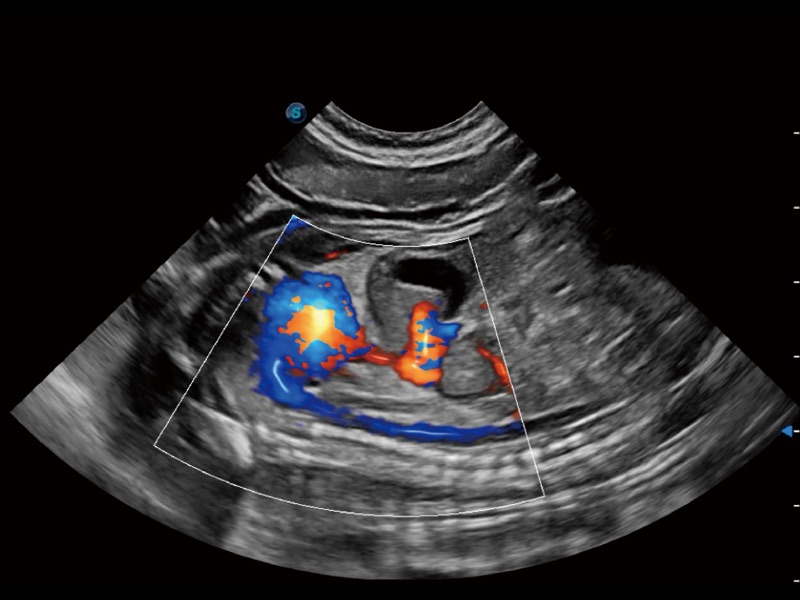

优异的基础图像

(犬)四腔心

(犬)四腔心MQA